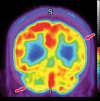

Neurodegenerative diseases are a devastating group of disorders that can be difficult to accurately diagnose. Although these disorders are difficult to manage owing to relatively limited treatment options, an early and correct diagnosis can help with managing symptoms and coping with the later stages of these disease processes. Both anatomic structural imaging and physiologic molecular imaging have evolved to a state in which these neurodegenerative processes can be identified relatively early with high accuracy. To determine the underlying disease, the radiologist should understand the different distributions and pathophysiologic processes involved. High-spatial-resolution MRI allows detection of subtle morphologic changes, as well as potential complications and alternate diagnoses, while molecular imaging allows visualization of altered function or abnormal increased or decreased concentration of disease-specific markers. These methodologies are complementary. Appropriate workup and interpretation of diagnostic studies require an integrated, multimodality, multidisciplinary approach. This article reviews the protocols and findings at MRI and nuclear medicine imaging, including with the use of flurodeoxyglucose, amyloid tracers, and dopaminergic transporter imaging (ioflupane). The pathophysiology of some of the major neurodegenerative processes and their clinical presentations are also reviewed; this information is critical to understand how these imaging modalities work, and it aids in the integration of clinical data to help synthesize a final diagnosis. Radiologists and nuclear medicine physicians aiming to include the evaluation of neurodegenerative diseases in their practice should be aware of and familiar with the multiple imaging modalities available and how using these modalities is essential in the multidisciplinary management of patients with neurodegenerative diseases.©RSNA, 2020.